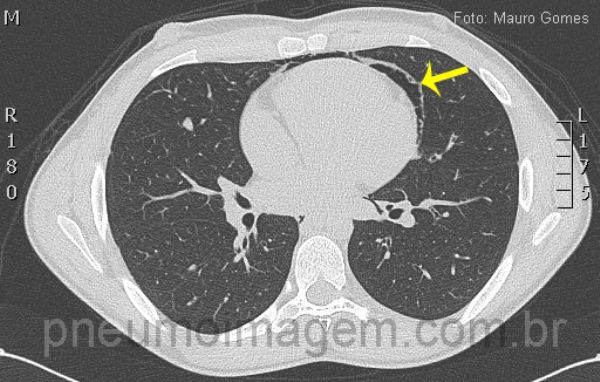

Neste corte observa-se o ar deslocando a pleura mediastinal e formando uma linha que circunda o coração (seta). Este é um jovem paciente do sexo masculino, com 19 anos, que sentiu dor torácica e dispneia durante uma partida de futebol.

In this section we observe the air displacing mediastinal pleura and shaping a line that surrounds the heart (arrow).

This is a young male patient, aged 19, he felt chest pain and dyspnoea during a soccer match.